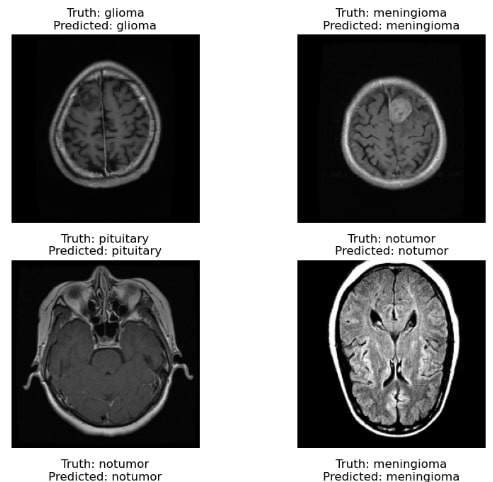

Figure 1: MRI Scans Showing Various Conditions: Glioma, Meningioma,a Non-Tumor Case and Pituitary Tumor

A few images from each class were visually inspected to understand dataset balance and quality, with examples shown in Figure 1. The varying nature of gliomas, meningiomas, pituitary tumors, and non-tumor cases hence brought a firm rationale before the model building and evaluating stages.